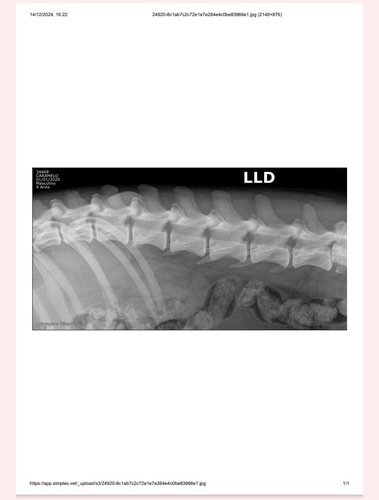

Olá, resgatei esse cachorro no dia 13/12 que foi atropelado próximo a empresa Klabin, recebeu ajuda para que ele fizesse um raio x e que passasse por uma consulta, sendo medicado com a ajuda de duas meninas do grupo da Causa Animal, visto que ele tem fraturas graves ele desapareceu até então.

Hoje 24/12 ele foi encontrado na rede de esgoto da empresa, segue bem machucado e foi trazido para a casa, ele precisa de uma cirurgia urgente se não irá sobreviver, conto com a sua ajuda para salvar a vida dele 🙏🏻